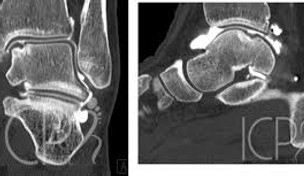

Arthrose et autres lésions ostéochondrales de la cheville

Motif de consultation :

Douleur persistante à la cheville, souvent associée à un gonflement et une sensation d’instabilité ou de blocage articulaire, particulièrement après un traumatisme ou une entorse.

Objectif de la prise en charge :

Réduction de la douleur, préservation de la fonction articulaire, et prévention de la progression de l’arthrose. Approche conservatrice en priorité.

Syndrome du carrefour postérieur de la cheville

Douleur à l’arrière de la cheville, exacerbée par des mouvements en hyperextension ou lors d’activités sportives impliquant des pointes de pied (danse, football). Une gêne mécanique ou un blocage peuvent également être ressentis.

Réduction de la douleur, amélioration de la mobilité postérieure de la cheville, et reprise progressive des activités en limitant les contraintes mécaniques. Approche conservatrice en priorité.